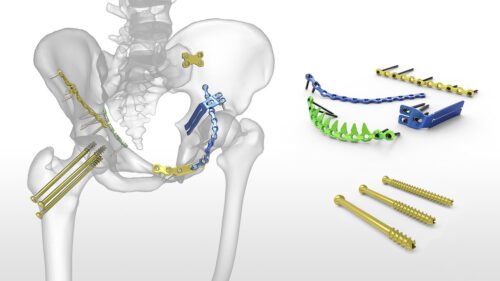

تثبيت الكسور بالشرائح والمسامير

ومع تقدم العلم اختلفت أنواع تثبيت الكسور جراحيًا تبعًا لنوع الكسر ومكانه ، وأيضًا تبعًا لعمر المريض وضمن هذه الأنواع هي تركيب الشرائح والمسامير الطبية، وتركيب المثبتات الخارجية والمسامير النخاعية ويحتاج الطبيب المعالج لعمل بعض الأشعات اللازمة لتحديد النوع المناسب لتثبيت الكسور.

ويقوم الطبيب بتثبيت الكسور والشروخ في جسم الإنسان بواسطة تركيب شرائح طبية ومسامير تساعد على التئام الكسر بشكل طبيعي وفي مكانه الصحيح مما يضمن للمريض استعادة حياته اليومية بشكل سريع وبدون ألم. وتناسب هذه الشرائح والمسامير بصفة خاصة الكسور القريبة من المفاصل.

ويتقبل جسم الإنسان هذه الشرائح والمسامير بشكل عادي فلا يعتبرها جسم غريب عنه أو يرفضها، وذلك لأن هذه الشرائح مصنوعة من عدة سبائك وهي: سبائك التيتانيوم وسبائك النيكل والكروم الممزوجة بالحديد وأيضًا سبائك الكوبالت.

تختلف بالطبع تبعاً للمادة المستخدمة في تصنيعها وسعرها، وأيضاً عل حسب البلد المصنعة لها ونوع الشرائح والمسامير المطلوبة.